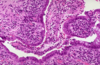

What is going on here? Arrows?

- Active colitis: crypt rupture + neutros attacking crypts + crypt abscesses

- Both UC and Crohn’s can have acute inflammation

- Crypt abscesses can rupture, making granuloma: this could be Crohn’s OR UC

- All you can dx from this image is ACTIVE COLITIS

What is going on here?

- Active colitis: ruptured crypts + crypt abscesses

- Chronic active colitis is consistent with IBD: could be UC or Crohn’s -> architectural changes indicate chronicity

- In UC, inflammatory process diffuse and generally limited to mucosa and superficial submucosa

- If granulomas are seen, and not associated with crypt rupture, can say this is suggestive of Crohn’s